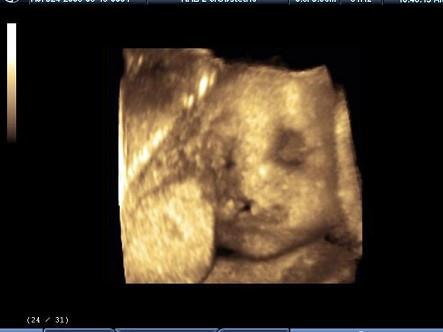

问题 超声检查如图,最可能的诊断是?(?)

选项 A.正常声像图 B.淋巴管囊肿 C.下颚裂 D.唇裂 E.上腭裂

答案 D